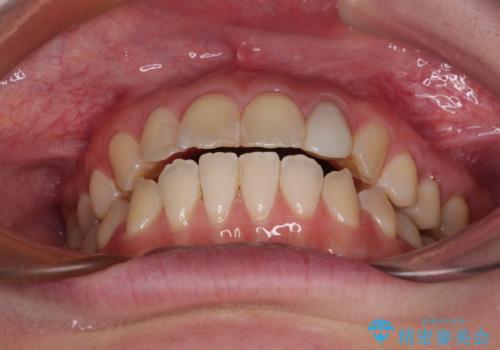

開咬を治す インビザラインによる矯正治療

- 上下前歯の開咬を気にして来院された患者様です。

開咬はインビザラインを用いると有意に改善ができるため、インビザラインによる矯正治療を行うこととしました。

途中1年8ヶ月ほど来院されず、久しぶりの来院後は治療が面倒とのことで、前歯の叢生や隙間に不十分な点が残った状態での終了となりました。